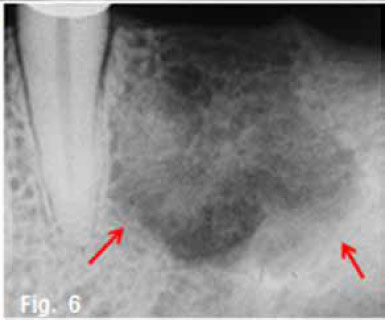

Figure 1 & 2 shows an aggressive lesion in a 14 year old male patient. The pantomograph show the lesion extending from the 36 to the 46. Expansion of the cortex and divergence of the roots is discernible. A histological diagnosis of a Central giant cell granuloma (CGCG) of the bone was made. The original term of CGCG was coined by Jaffe in 1953, when he suggested that this lesion should be distinguished from the Central giant cell tumour (GCT) of bone. Jaffe believed that the CGCG is a reactive lesion, whereas the CGT is a neoplasm. Central giant cell granuloma of the jaws is considered to be a fairly common benign reactive lesion. It is characterized by the presence of numerous multinucleated giant cells. The CGCG most commonly affects young people and over 50% of cases occur in the first two decades of life. The average age of occurrence is 21 years, with a range of 3 to 68 years. Females are affected slightly more than males. The mandible is affected in the majority of cases, with the anterior segments being affected more often than the posterior. Radiographically the lesion is essentially radiolucent, often with a multilocular, soap bubble appearance (Fig.3). A rather marked expansion with thinning of the cortical plates is a characteristic finding (Fig.4). The tumour usually destroys the lamina dura and causes displacement of the teeth (Figs.2 & 3). It may lie in intimate contact with the teeth, causing very few changes; in other areas it may cause extensive root resorption. This root resorption is usually irregular and leaves a ragged surface in contrast to the smooth resorption seen in association with cysts. According to Langlais et al.(1994), CGCG's can present with an aggressive or non-aggressive behaviour. The basis for this division consisted of histologic, clinical and radiological factors. The radiological features of the aggressive type include resorption of adjacent root apices, perforation of the expanded cortex and a diameter exceeding 2cm; nonaggressive lesions are characterized by the absence of root resorption, intact cortices and a diameter smaller than 2cm. A peripheral variant of this lesion occurs in the gingiva and produces an epulis-like soft tissue mass in the gingival region. In a edentulous area it may result in a nodule or swelling on the alveolar ridge and may present radiologically with a typical "peripheral cuffing" (red arrows, Fig.5). The CGCG are known to recur, and recurrence is a feature of the aggressive type and may require curettage plus peripheral ostectomy A histological diagnosis of CGCG must always be followed by a workup for the possibility of the presence of a "Brown" tumour of hyperparathyroidism.